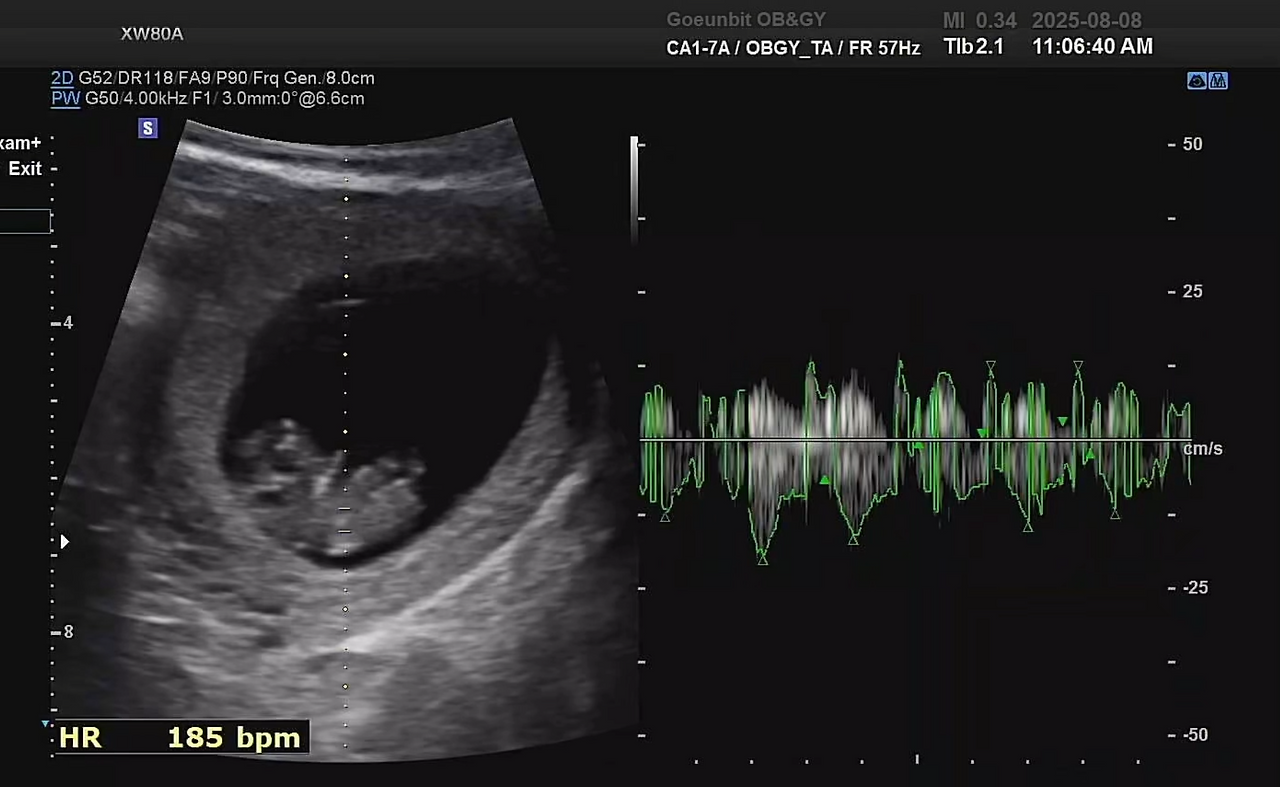

2주 만에 병원에 가서 배로 초음파를 봤지만, 느낀 건 “아직 잘 있구나” 하는 안도감뿐이었다.

10주 차